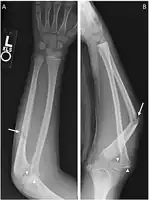

| X-ray of Monteggia fracture of right forearm | |

The Monteggia fracture is a fracture of the proximal third of the ulna with dislocation of the proximal head of the radius. It is named after Giovanni Battista Monteggia.[1][2]